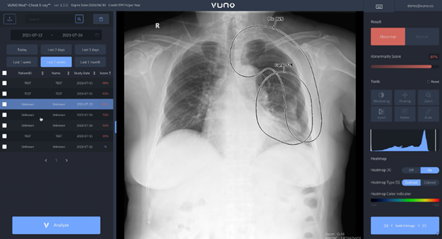

뷰노가 이처럼 다양한 사업 모델을 선보일 수 있는 배경에는 ’뷰노메드 체스트 엑스레이™‘ 등 뷰노 AI 솔루션이 바탕이 됐다.

실제 뷰노 AI 솔루션은 영상의학 등 전 세계적으로 권위 있는 임상 학술지에서 객관적인 근거를 확보하고 그 가치와 유효성을 입증하고 있다.

특히 AI 알고리즘 연산 최적화로 모델 경량화를 구현했으며, 기존 의료기기 하드웨어 내 연산 자원으로도 AI 서비스를 제공할 수 있다.

따라서 다양한 업체 엑스레이 장비에 용이하게 탑재할 수 있고, 국내외 모든 의료 환경에 적용할 수 있어 다방면으로 사업 전개가 가능하다.